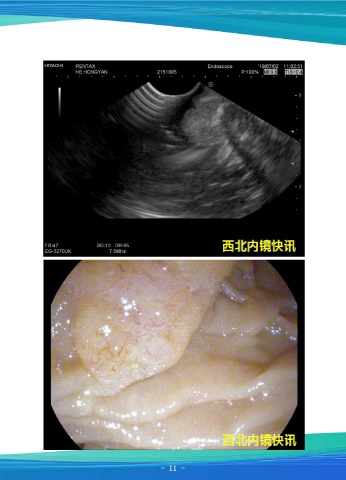

超声内镜示:见胰腺回声弥漫增高,胰头部分呈网格状,胰管壁回声正常,胆总管

未见增宽,乳头见广基增生性隆起,超声扫描见乳头下方肠壁粘膜层增生,血管分布正

常,截面直径9.9x8.4mm,胆胰管汇合正常,壶腹未见受累。